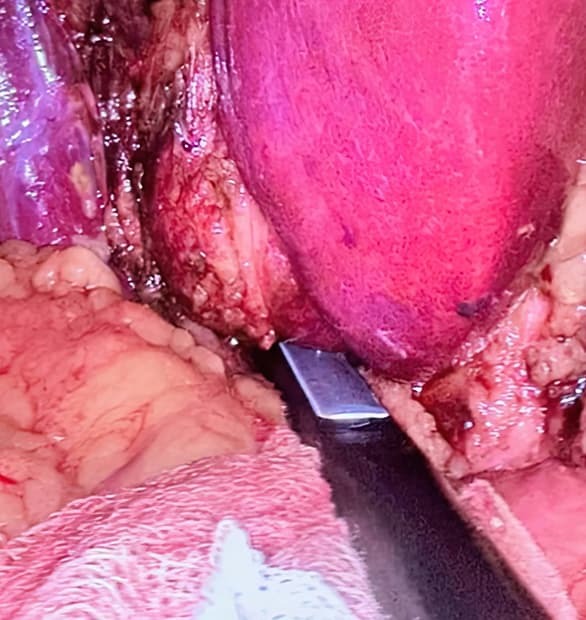

В феврале в Гродненской университетской клинике была впервые выполнена лапароскопическая анатомическая резекция s 4b и s 5 сегментов печени по поводу очагового образования данной локализации с лимфодиссекцией гепатодуоденальной связки у пациента с перемещенной общей печеночной артерией (исходящей из верхней брыжеечной артерии).

С целью точного и анатомичного выделения желчных, артериальных и венозных структур, входящих в портальные триады удаляемых сегментов, использовался способ экстраглиссонового интрапаренхиматозного их выделения. Данный способ впервые в мире был предложен советским хирургом-гепатологом Эдуардом Гальпериным в 1980-х годах во время выполнения открытых резекционных вмешательств на печени. Впоследствии метод и его модификации активно развивали и популяризировали японские хирурги, в частности Масатоши Макуучи и Н. Кобаяши, разработавшие свои варианты глиссоновой изоляции. Бразильским хирургом Марселем Аутраном Мачадо он был популяризирован и модифицирован в том числе и для лапароскопических и роботических резекций печени, не связанных с родственной трансплантацией.

vcvfghhgffy76Метод хорош своей воспроизводимостью, способствует освоению безопасной технологии резекций печени более широким кругом хирургов и значительно ускоряет выполнение оперативного вмешательства. Вместе с тем требует учета индивидуальных анатомических вариаций в каждом конкретном случае и тщательного изучения данных КТ и МРТ в дооперационном периоде.

Интраоперационно с целью более точной топической локализации образования во время резекции и его соотношения с желчными протоками, артериальными и венозными сосудами печени выполнялось ультразвуковое исследование с использованием лапароскопического ультразвукового датчика.